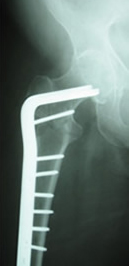

The device, which won AO approval in 2004, makes repair of hip fractures a reality for older adult patients who previously were not good candidates for procedures using conventional hip screw technology.

The new device is a huge technological leap in hip fracture surgery and improves patient care and recovery time. Offering several advantages over traditional screw-type implants that are currently used to treat hip fractures, this device:

- Provides better stability when plates are inserted next to the fractured bone, providing less of a chance of movement or loosening of the bone and the plates.

- Requires less torque and less removal of good bone to insert the helical blade, which can reduce the risk of complications during surgery.

- Provides patients with fracture repair that is much more resistant to failure than conventional devices.

| Hip Hemiarthroplasty | DHHS (Dynamic Helical Hip System) in an intertrochanteric fracture |